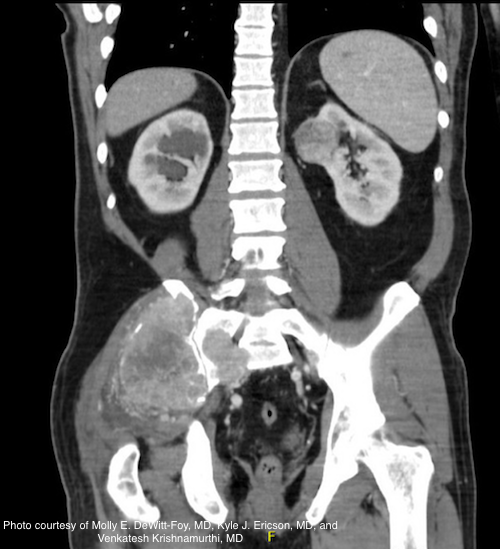

A recent study suggests experimental "texture analysis" of renal masses via computed tomography scan holds promise as a technique to allow more effective risk stratification.